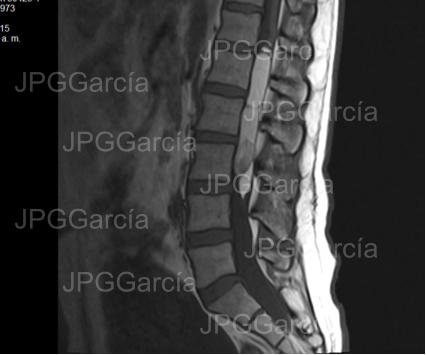

Estudio de resonancia magnética prequirúrgico que demuestra

una lesión tumoral torácica relacionada a un meningioma

RESECCIÓN MICROQUIRÚRGICA DE MENINGIOMA TORÁCICO

Estudio de resonancia magnética prequirúrgico que demuestra una lesión tumoral torácica relacionada a un meningioma